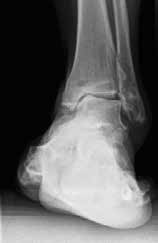

Das besondere Merkmal der Arthrose des OSG ist das relativ junge Alter der Patienten im Vergleich zur Arthrose anderer Gelenke der unteren Extremität, da die meistens zugrunde liegenden Traumata Sportunfälle sind. Zusätzlich werden ein schnellerer Funktionsverlust des Gelenks und eine beschleunigte Progression der Erkrankung bis zum Erreichen des Endstadiums (innerhalb von 10 bis 20 Jahren) beobachtet 9 (Abb. 2a). Negativ beeinflussende Faktoren für die Entwicklung einer Arthrose des OSG sind: Achsfehlstellungen oder angeborene Deformitäten der unteren Extremität, Muskeldysbalance 10, angeborene oder erworbene ligamentäre Fehlentwicklungen, Alter, Geschlecht und genetische Prädisposition 11.

Weiterhin führen Fehlstellungen im Rückfuß zu statischen und dynamischen Überlastungen, da sich bei Varusfehlstellung (Abb. 2a) das Zentrum der Kraftübertragung nach medial und bei Valgusfehlstellungen nach lateral verlagert 47. Die Achillessehne wirkt durch ihren Zug zusätzlich invertierend bei Varusfehlstellung und evertierend bei Valgusfehlstellung auf den Rückfuß ein 48. Möglichkeiten der operativen Therapie sind entweder die einfache Umstellungsosteotomie der distalen Tibia und Fibula als rein supramalleoläre Osteotomie mit dem Ziel einer Überkorrektur des distalen Tibiagelenkflächenwinkels von 3 bis 5° 49 oder die kombinierte Osteotomie an Bein und Rückfuß (Abb. 2b) mit oder ohne Weichteileingriff je nach Topographie der Achsfehlstellung 50. Weitere Möglichkeiten sind die Calcaneusosteotomie, meist als ergänzende Osteotomie nach Wiederherstellung der korrekten Achse (Abb. 2b) im Sinne einer Verschiebeosteotomie, um die Zugrichtung der Achillessehne zu zentrieren, und die Osteotomie der medialen Säule, die bei durch Valgusfehlstellung induzierter Abflachung des medialen Längsgewölbes indiziert sind. Hierbei werden zusätzlich korrigierende Arthrodesen des I. Strahls (Naviculo-cuneiforme-Gelenk, Tarsometatarsalgelenk) oder plantarflektierende Osteotomien (Cuneiforme I oder Metatarsale I) durchgeführt 51.

In ausgeprägten Fällen von Arthrose, oft mit Instabilität im oberen Sprunggelenk (Abb. 7), schwerwiegendem Funktionsverlust und starker Schmerzausprägung, ist nach wie vor die Arthrodese die Therapieoption der Wahl. Dadurch sollen die Achskongruenz wiederhergestellt und die Schmerzen eliminiert werden. Gleichzeitig bedeutet dieser Schritt jedoch, dass keine weitere operative Eskalation mehr möglich ist. Meist kommen die tibiotarsale oder tibiatalar-calcaneare Arthrodese zum Einsatz. Entscheidend für die Wahl des Arthrodeseverfahrens sind der Schweregrad der degenerativen Gelenkveränderungen, der Schmerz und die Stellungsverhältnisse im Subtalargelenk.